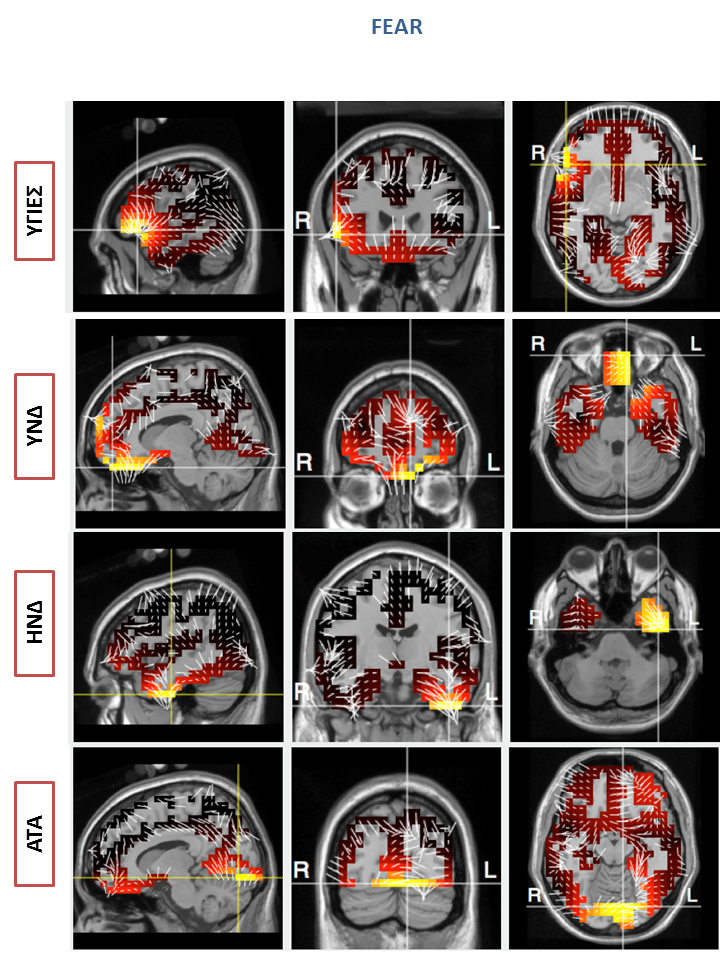

Ενώ όπως αναμενόταν, στην περίπτωση της ομάδας ΑΤΑ, οι ασθενείς παρουσίασαν την ελάχιστη ενεργοποίηση συγκεκριμένων περιοχών συγκριτικά με τις άλλες τρεις ομάδες. Σημαντικές διαφορές παρατηρήθηκαν επίσης στην τοπογραφική ανάλυση όπου επιβεβαίωσαν αυτή τη διαφορά, καθώς η βαρύτητα της νόσου αποδείχθηκε ότι επηρεάζει σημαντικά την ενεργοποίηση συγκεκριμένων περιοχών του εγκεφάλου που διαδραματίζουν σημαντικό ρόλο στην αντίληψη συναισθημάτων (Εικόνα 1). Συγκεκριμένα, παρατηρήθηκε μικρότερη ενεργοποίηση και δραστηριότητα στο μετωπιαίο και κροταφικό λοβό των συμμετεχόντων με ΥΝΔ σε σχέση με του υγιείς καθώς επίσης και μεταξύ των ασθενών με ΗΝΔ και ΑΤΑ (Εικόνα 2).

2) Εικόνα 2: Καταγραφή μικρότερης ενεργοποίησης και δραστηριότητας στο μετωπιαίο και κροταφικό λοβό των συμμετεχόντων με ΗΝΔ σε σχέση με τους υγιείς καθώς επίσης και των ασθενών με ΗΝΔ και ΑΤΑ

Εικόνα 2